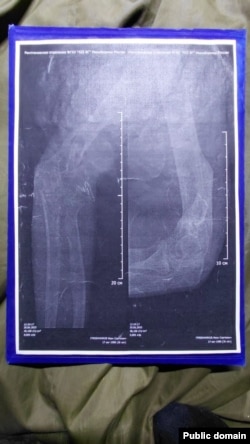

"Не проводят ВВК (военно-врачебная комиссия), никакой медкомиссии, в теле пуля, рука переломана. Домой не отпускают", – говорит Гребенников на камеру, когда его в составе 35-й отдельной гвардейской мотострелковой бригаде (в/ч 41659) везут вместе с другими пленными после обмена в Донецк. До этого Гребенников записывал видео, как его за отказ возвращаться на фронт посадили в камеру в его воинской части.

Согласно медицинским документам Гребенникова, 30 июня 2025 года врач-невролог провел осмотр и поставил диагноз, указав категорию годности к военной службе – "Д" (полностью не годен). Невролог дал направление Гребенникову в Брянку (город в Луганской области Украины) для "лечения, прохождения военно-врачебной комиссии (ВВК) и официального определения категории годности". Однако все назначения врача командование проигнорировало – Гребенникова и других раненых, возвращенных после плена, насильно отправили на фронт.

– Нам казалось, что после возвращения из плена нас хотя бы лечить будут. Куда там – нам внаглую поменяли категории на фальшивые – мне, например, мою "Д" заменили на "Б" (годен к службе с незначительными ограничениями), хотя у меня правая рука как была в нескольких местах перебита, так и висит. У меня до сих пор пуля в теле – даже не оперировали, – говорит Иван. – И нас таких очень много – на костылях, в гипсе. Им просто по**й, везут на Донецкое направление калек.